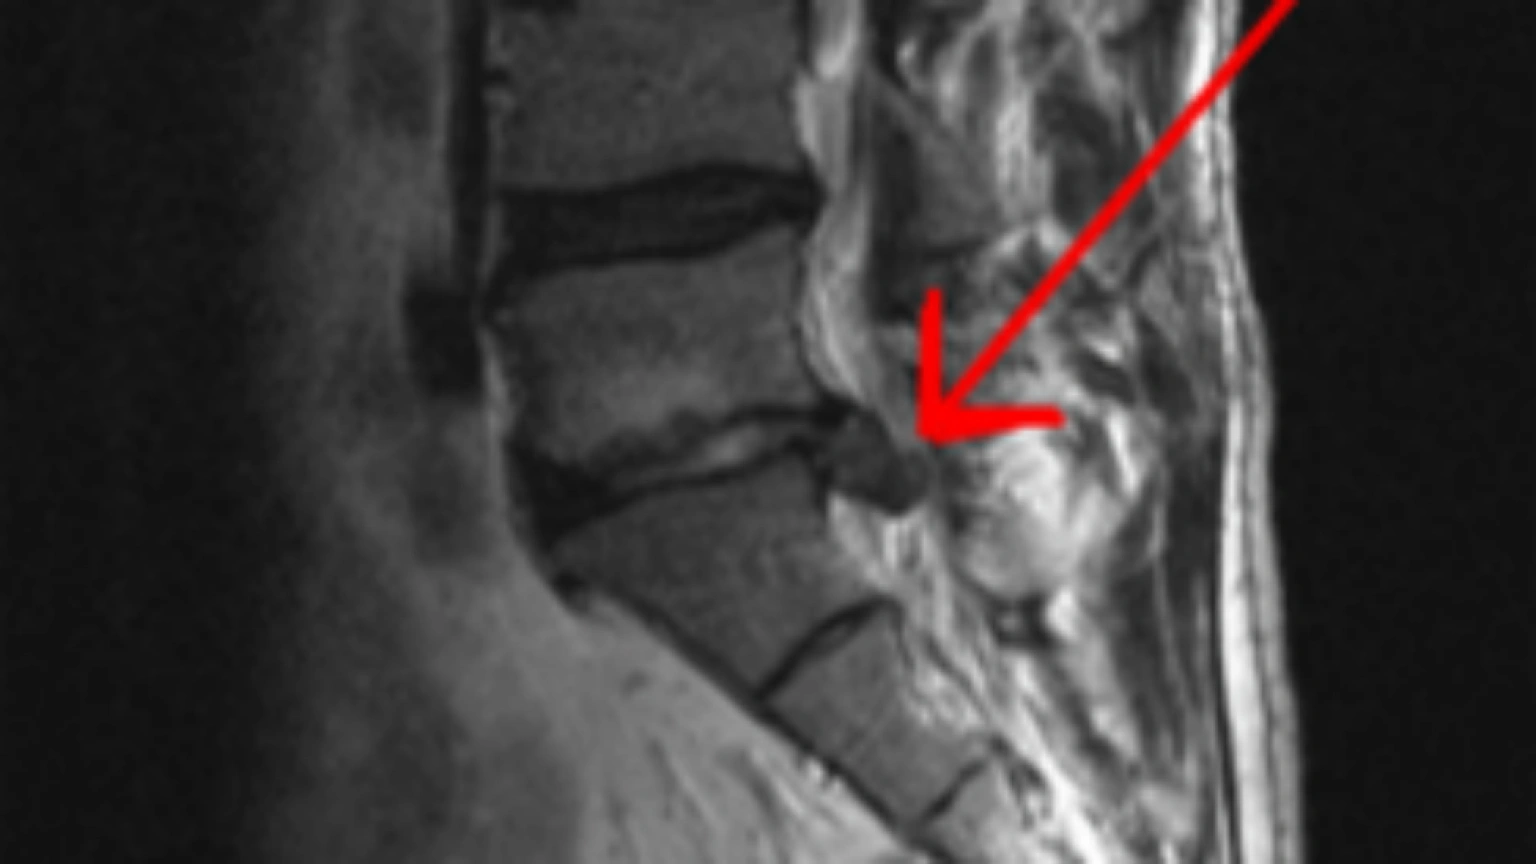

Sólo el 1% de las hernias discales se operan